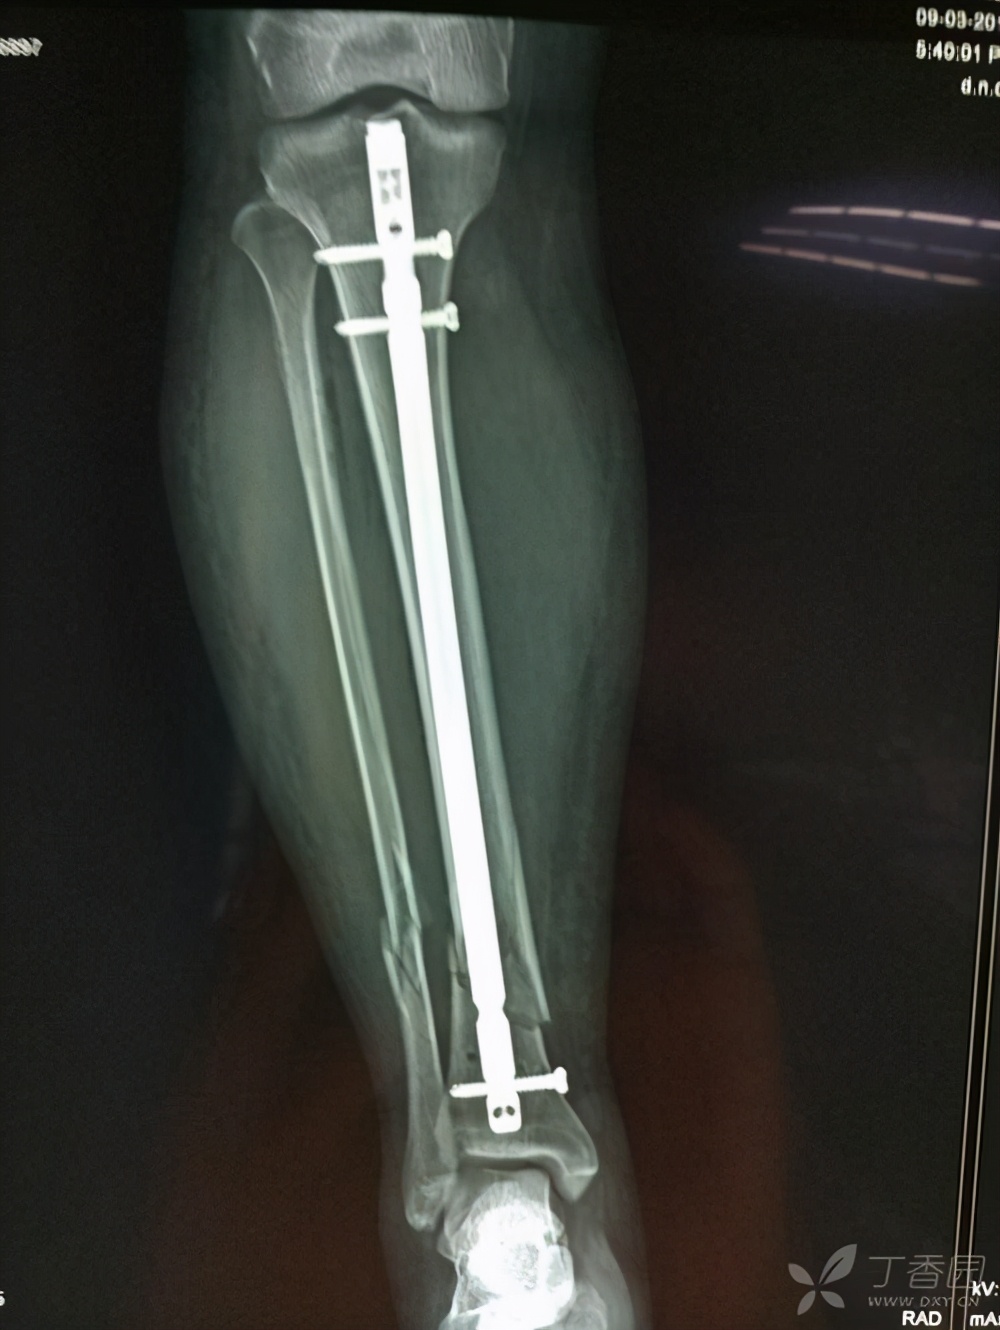

1、髓内钉:除了正在发育的小孩子(多用一种与成人不同的弹性髓内钉),不管多大年纪,只要没有出现明显内固定物导致的不适都是可取可不取的。什么叫髓内针呢,就是把内固定物放到你的骨髓腔中,有利于骨折更好的愈合不懂看下面图片。当然如果你是年轻人可以来取,如果是上了岁数的老人如果没有对身体造成什么不适,还是不建议取出

胫骨髓内钉